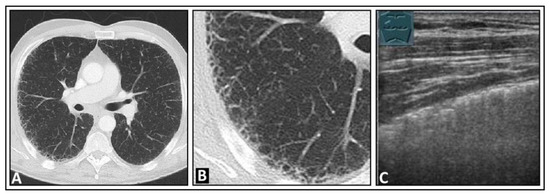

5. Pneumonia